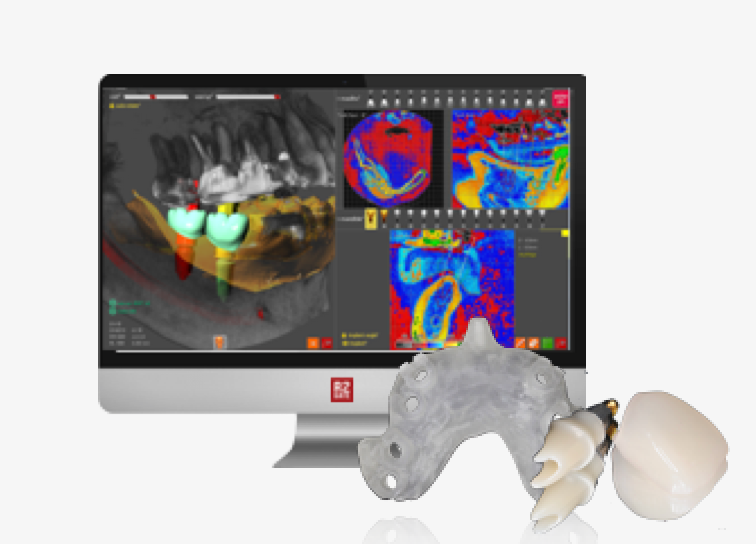

R2STUDIO™ + R2GATE® facial analysis

R2STUDIO: ONE STEP collection & digitization of patient data within 10 min (CBCT + 3D facial scan + STL dentition file)

R2GATE® facial analysis: unique function that defines mid-facial plan, skeletal asymmetries, & esthetic problems

FACEGIDE™

Customized orthognathic solutions

Saw Guides

- Customized for each patient to ensure precise bone incisions & deletions

FACEGIDE Plates

- Customized for each patient

- Reduced surgery time as no need to bend or cut customized plates